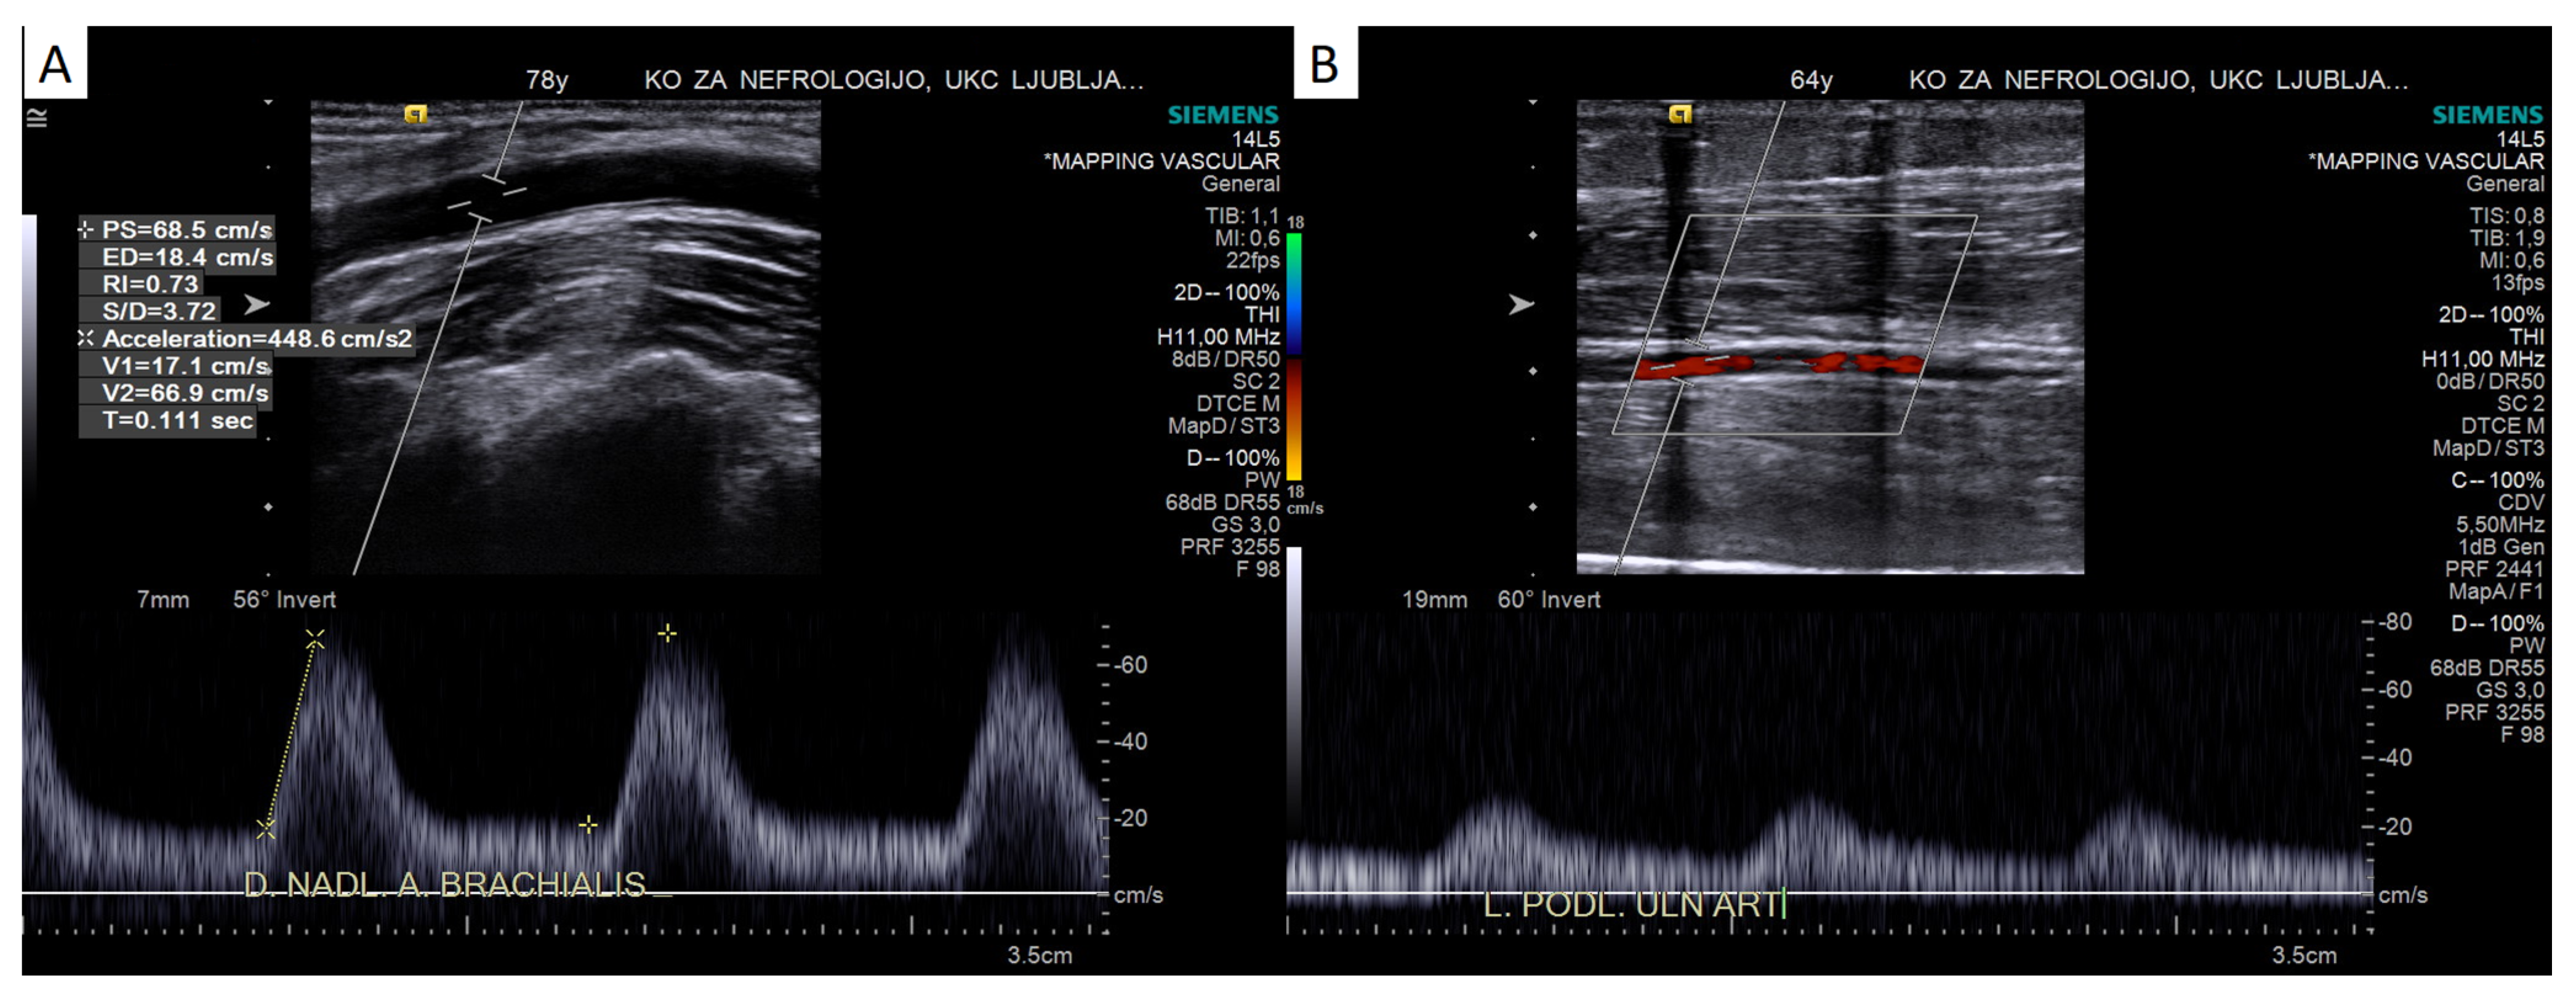

4.2.2. Pulsed-Wave Doppler Assessment

Doppler Curve Assessment, Acceleration Parameters